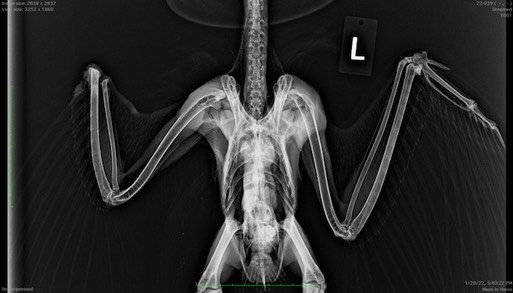

It wasn’t any better for Red-tailed Hawk 22-038 who had multiple fractures in its right wing. Even with a surgical repair, it was almost certain the ulna and radius would fuse as the fractures healed, preventing the hawk from being able to fly.

Great Horned Owl 22-039 was found in Hermiston with a severed right wing. Again, there was nothing we could do and the owl was euthanized.